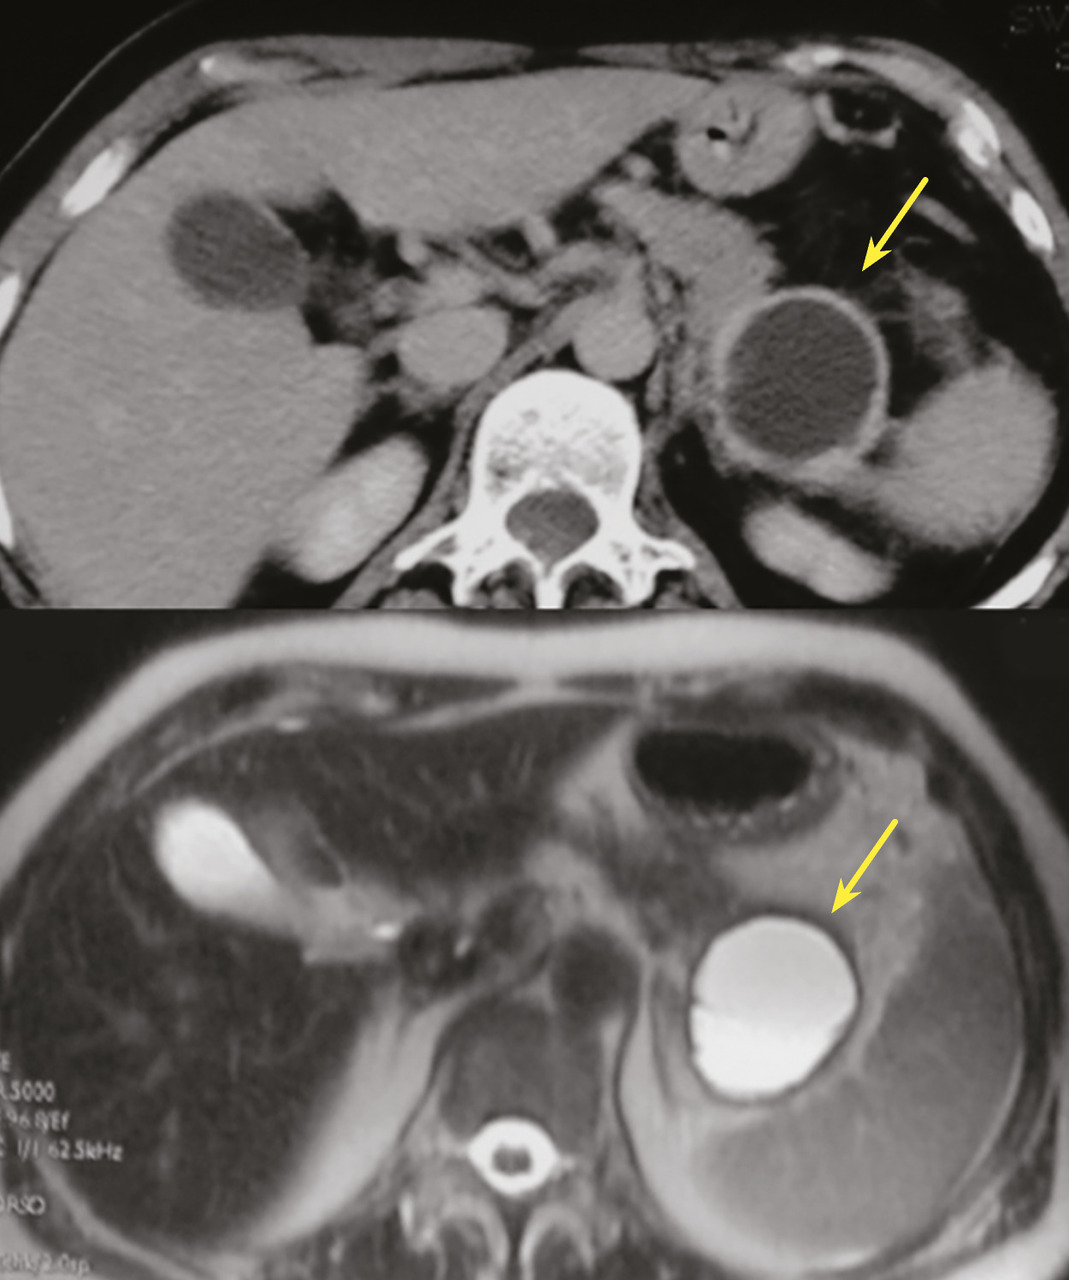

Cystadénome séreux

Il s’agit d’une tumeur kystique multiloculaire pouvant mesurer de 1 à plus de 20 cm, avec un aspect de «  cicatrice  » fibreuse centrale, parfois calcifiée (fig. 4). Ils sont plus fréquents chez les femmes (3 femmes pour 1 homme) avec un âge médian au diag­nostic autour de 60 ans. Ils sont le plus souvent de découverte fortuite ou secondaire à l’exploration de douleurs abdominales aspécifiques. Leur taille est stable dans le temps dans 60 % des cas, ou avec une croissance lente (4 mm/an). Les complications sont rares, et la dégénérescence exceptionnelle (moins de dix cas décrits dans la littérature), la surveillance n’est donc pas nécessaire. Pour les exceptionnelles lésions volumineuses (10 % de séreux macrokystiques), une chirurgie peut se discuter12 si elles sont à l’origine de symptômes invalidants.